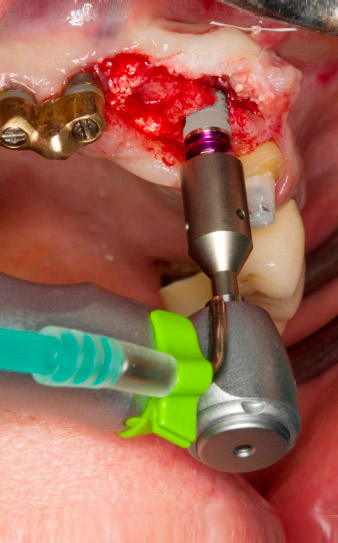

pilot drilling is performed with the new Implantmed and the WS-56 L contra-angle handpiece

Fig. 2: Two months later the pilot drilling is performed with the new Implantmed and the WS-56 L contra-angle handpiece (programme P1, ratio 1:1). The cooling is performed via the spray tube positioned on the left (for right-handed users).

Tapping with the WS-75 L contra-angle handpiece

Fig. 3: Tapping with the WS-75 L contra-angle handpiece at a ratio of 20:1 (programme P4). Implantmed’s high torque, the hexagon chucking system for reliable power transmission and the automatic reversal of the direction of rotation when resistance gets too high prove particularly helpful here.